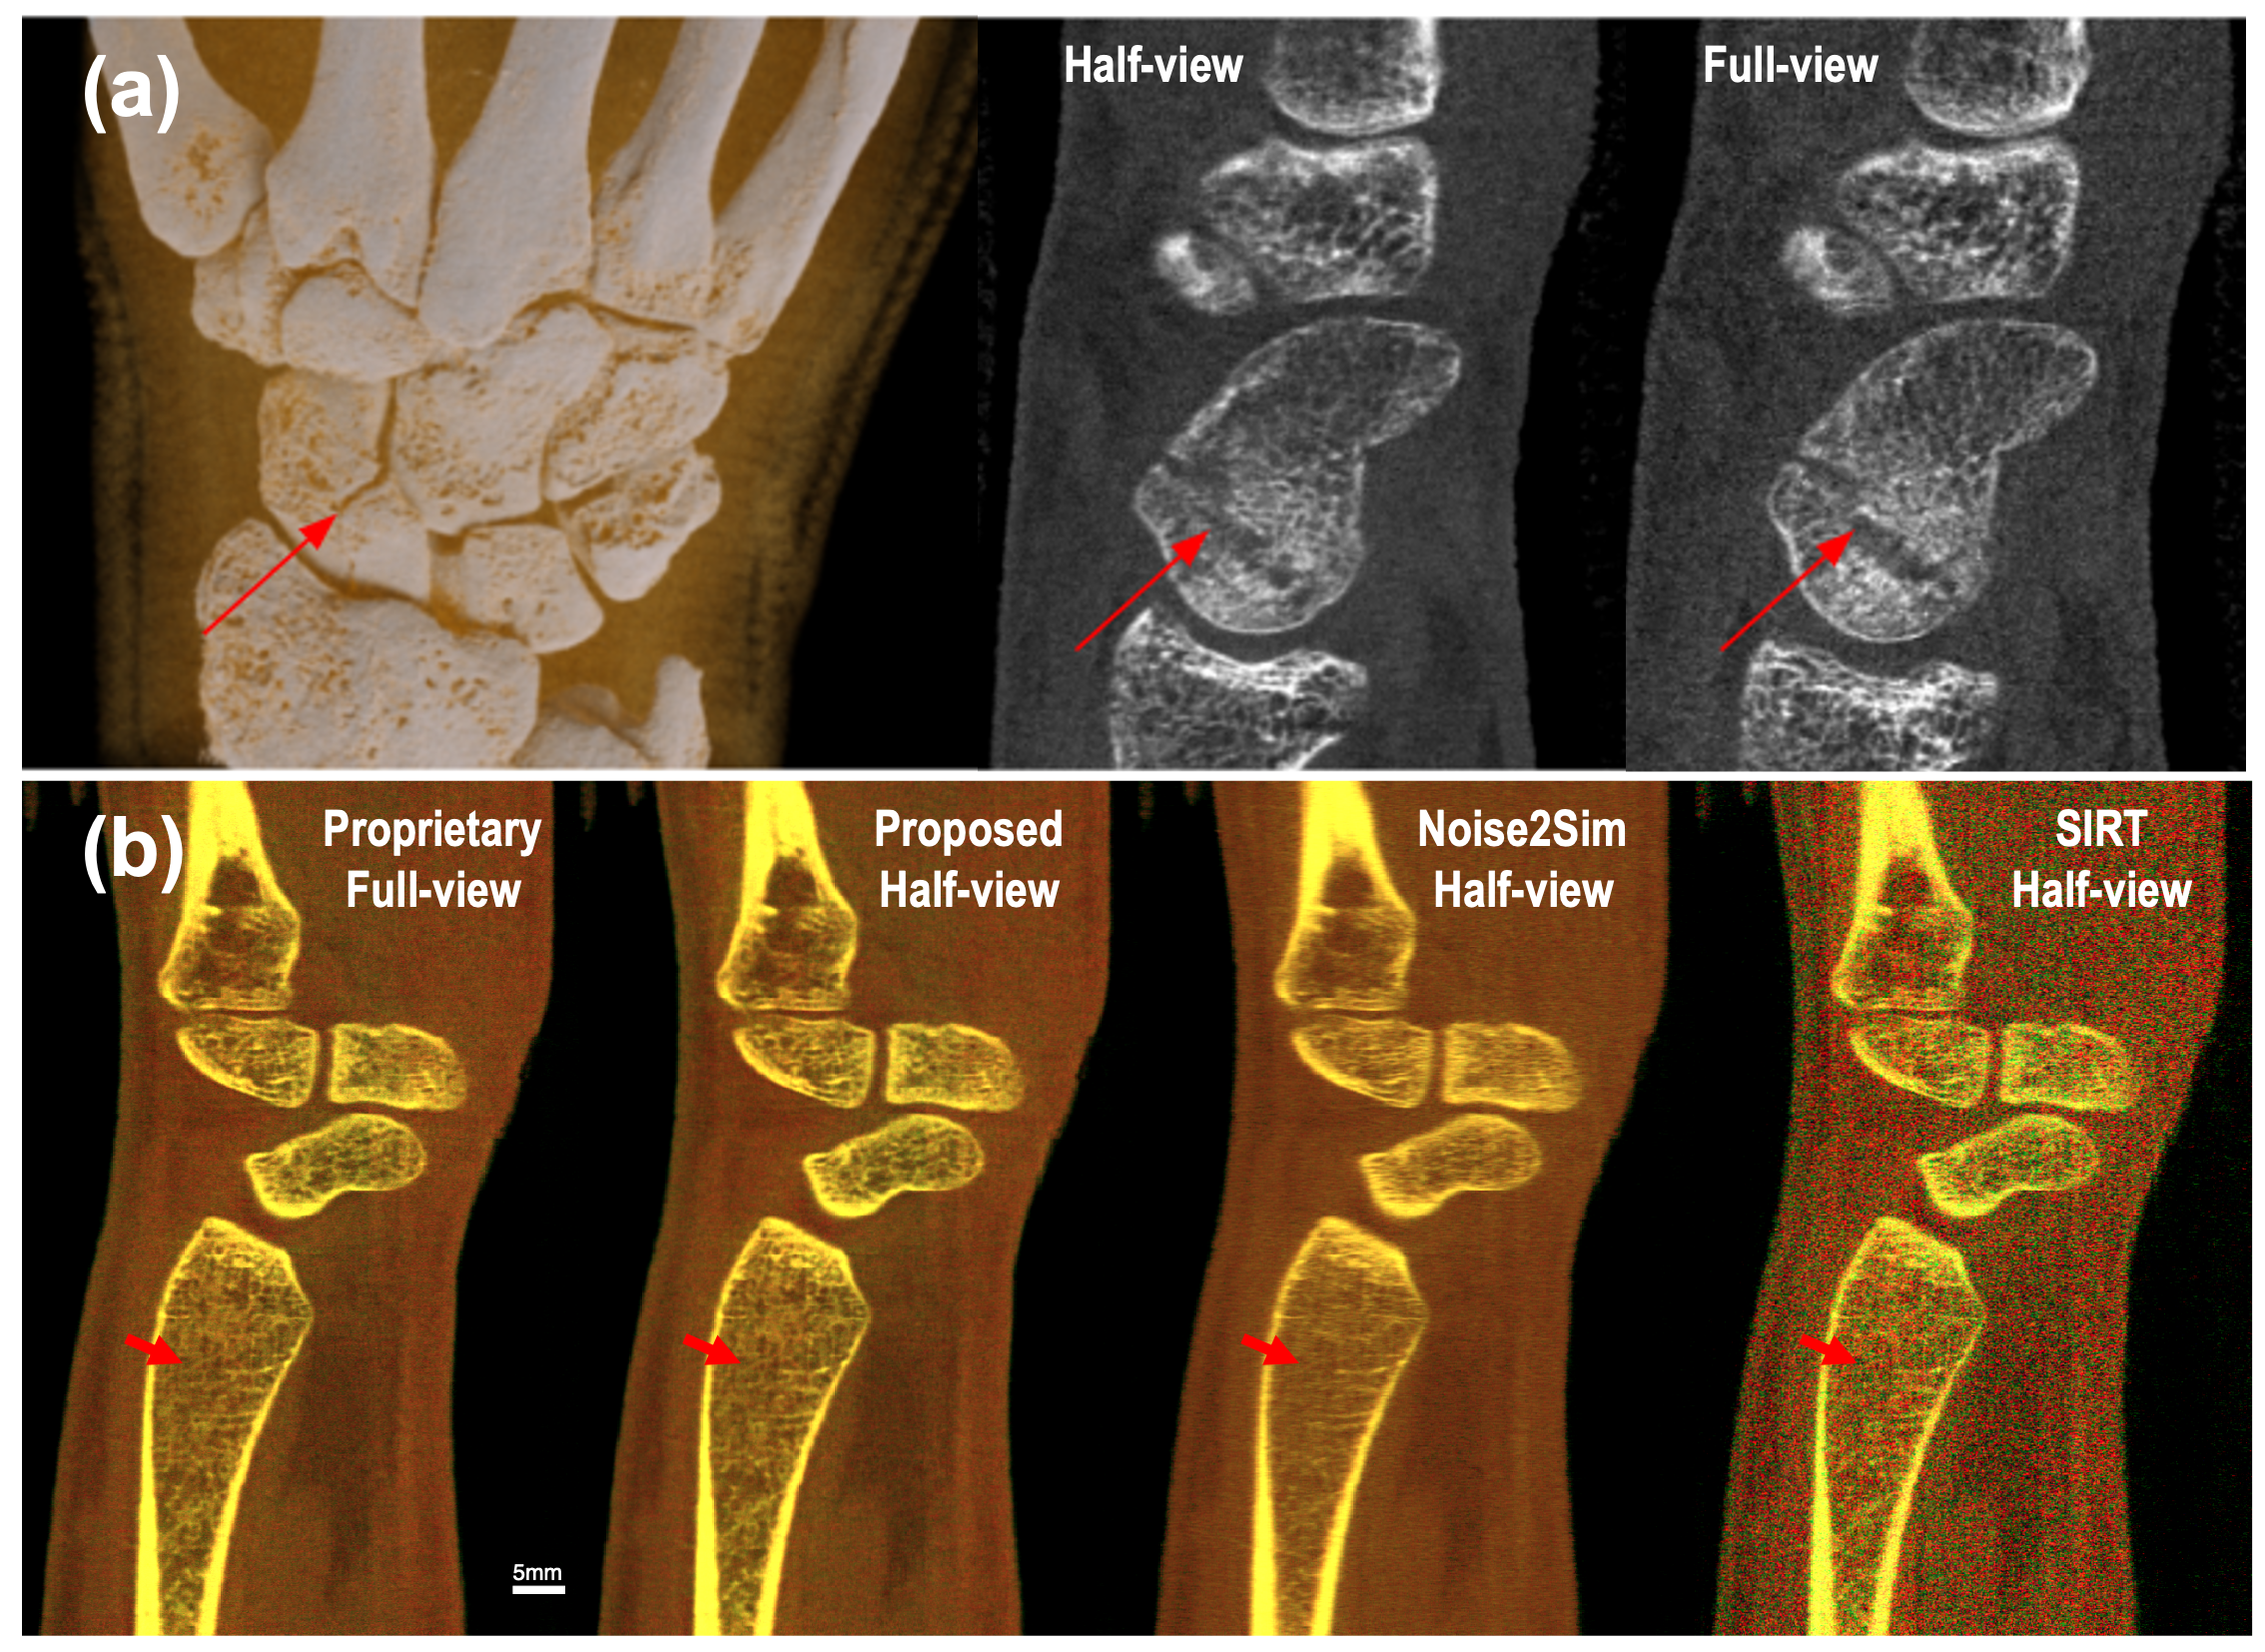

The radiologists were presented with 500 images from each patient (three energy bins 740keV740𝑘𝑒𝑉7-40keV, 5060keV5060𝑘𝑒𝑉50-60keV and 70118keV70118𝑘𝑒𝑉70-118keV) in the axial, coronal and sagittal formats. The sagittally reformatted images reconstructed using both methods and 3D rendering image using the standard method are shown in Fig. 7(a). The images were reviewed using InteleViewer (Intelerad Medical Systems). The image metrics assessed in the study were based on the “European guidelines on quality criteria for CT” for bones and joints [49]. The images were assessed on seven image quality criteria, including the visibility and sharpness of the cortical and trabecular bone, adequacy in soft tissue contrast for the visualisation of tendons, muscle and ligaments, as well as the effect of image noise (quantum noise) and artifact on the image quality.

Additionally, we also compare our result with that obtained by applying the state-of-the-art unsupervised learning method Noise2Sim [27] to the multi-channel reconstructions using 320 SIRT iterations for each channel. Despite significant enhancement over SIRT reconstruction from half-view dataset, Noise2Sim results demonstrate insufficient image quality (suffering from image blur and loss of fine structures) as shown in Fig. 7(b), hence, they are excluded from the reader study.

Refer to caption

Figure 7: Sagittal reformat of a wrist joint reconstructed using standard and proposed methods respectively. (a) From left to right are 3D rendering of standard reconstruction, half-view and full-view images of channel 50-60keV. The arrow points to scaphoid fracture. (b) Color visualization of our three-channel reconstruction via linear blending [50] in reference to standard full-view result and noise2sim half-view result. Our result demonstrates high fidelity in both spectral values (same color tone and brightness as the full-view reference) and spatial structures (sharp and accurate fine details as pointed by the red arrow).